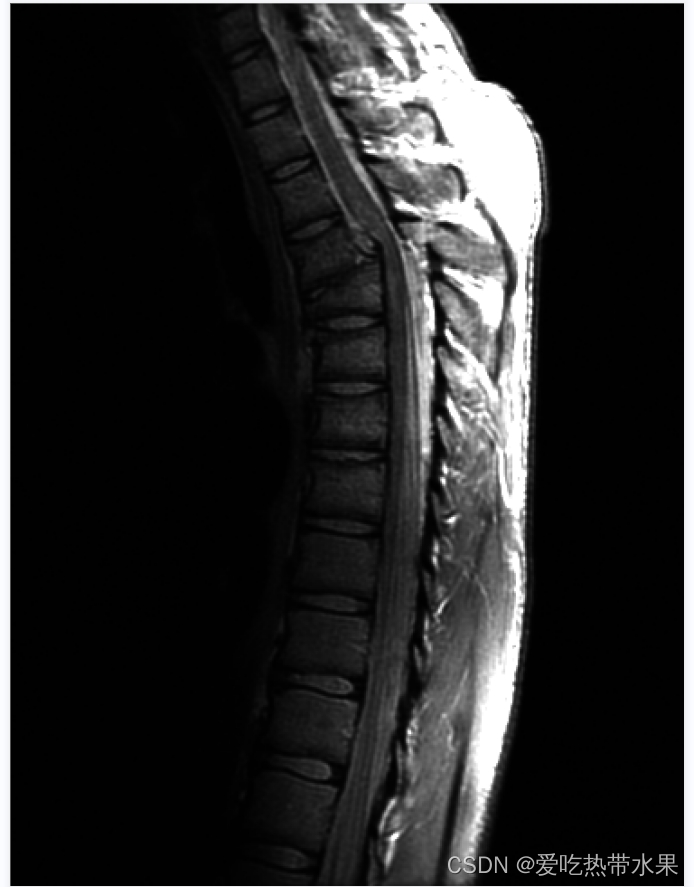

cv::Mat readImg = cv::imread("Fig0308(a)(fractured_spine).tif");

cv::cvtColor(readImg, image1_gray, COLOR_BGR2GRAY); //灰度化

for(int i = 0; i < image1_gray.rows; i++)

{for(int j = 0; j < image1_gray.cols; j++){image1_gray.at<uchar>(i, j) = qPow(image1_gray.at<uchar>(i, j), 0.7);}

}

cv::normalize(image1_gray, image1_gray, 0 , 255, NORM_MINMAX);

cv::imshow("image",image1_gray);

cv::waitKey(0);

整体变亮.jpg | 原图.jpg |